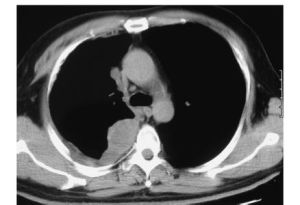

2.胸部CT檢查

可以顯示腫瘤的大小及範圍。了解腫瘤是否超越同側胸腔邊界,進犯縱隔結構,或侵襲膈肌及膈肌下結構是非常重要的。典型表現為:可顯示患側胸廓縮小、胸膜顯著增厚、胸腔積液,少數病例可見胸膜斑。